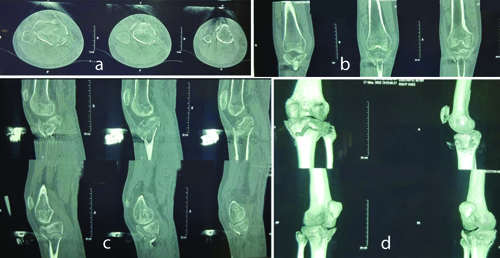

The medial column is often fixed first. Initially, the lateral column was reconstructed when the medial condyle was severely comminuted. In cases where the fragment was posterior, an open posteromedial approach was employed. By adequately retracting the gastrocnemius and pes anserinus, the posteromedial fragment was made visible. The anatomical reduction was achieved by adequately visualising the fragment. Fracture reduction was confirmed under fluoroscopic guidance. Then, a 3.5-mm medial proximal tibial Locking Compression Plate (LCP) or T buttress plate was used to hold the reduced fracture in place. For the anterolateral technique, a lazy ‘S’ incision was made parallel to the tibial shin, just lateral to the tibial tuberosity. Anatomical lateral locking plates, ‘L’ shaped buttressing plates, or lateral tibial raft plates were fixed to the lateral surface after achieving satisfactory reduction under the C-arm. Tibial tuberosity avulsions were fixed with thin-profile distal fibular plates in buttressing mode for all patients [Table/Fig-1a-c]. A contralateral thin-profile distal fibular plate was utilised to provide a buttressing effect. This plate was preferred as it could sit flush over the tibial tuberosity, offering a broad buttressing effect on the tuberosity fragment. Other precontoured plates did not sit flush over the tuberosity fragment. The intraoperative images showing plating has been depicated in [Table/Fig-2]. CT knee images with Schatzker type V fracture and tibial tuberosity avulsion fracture has been depicted in [Table/Fig-3].

CT knee images with Schatzker type V fracture and tibial tuberosity avulsion fracture (a) Axial section, (b,c) Coronal section and (d) 3D reconstruction image.